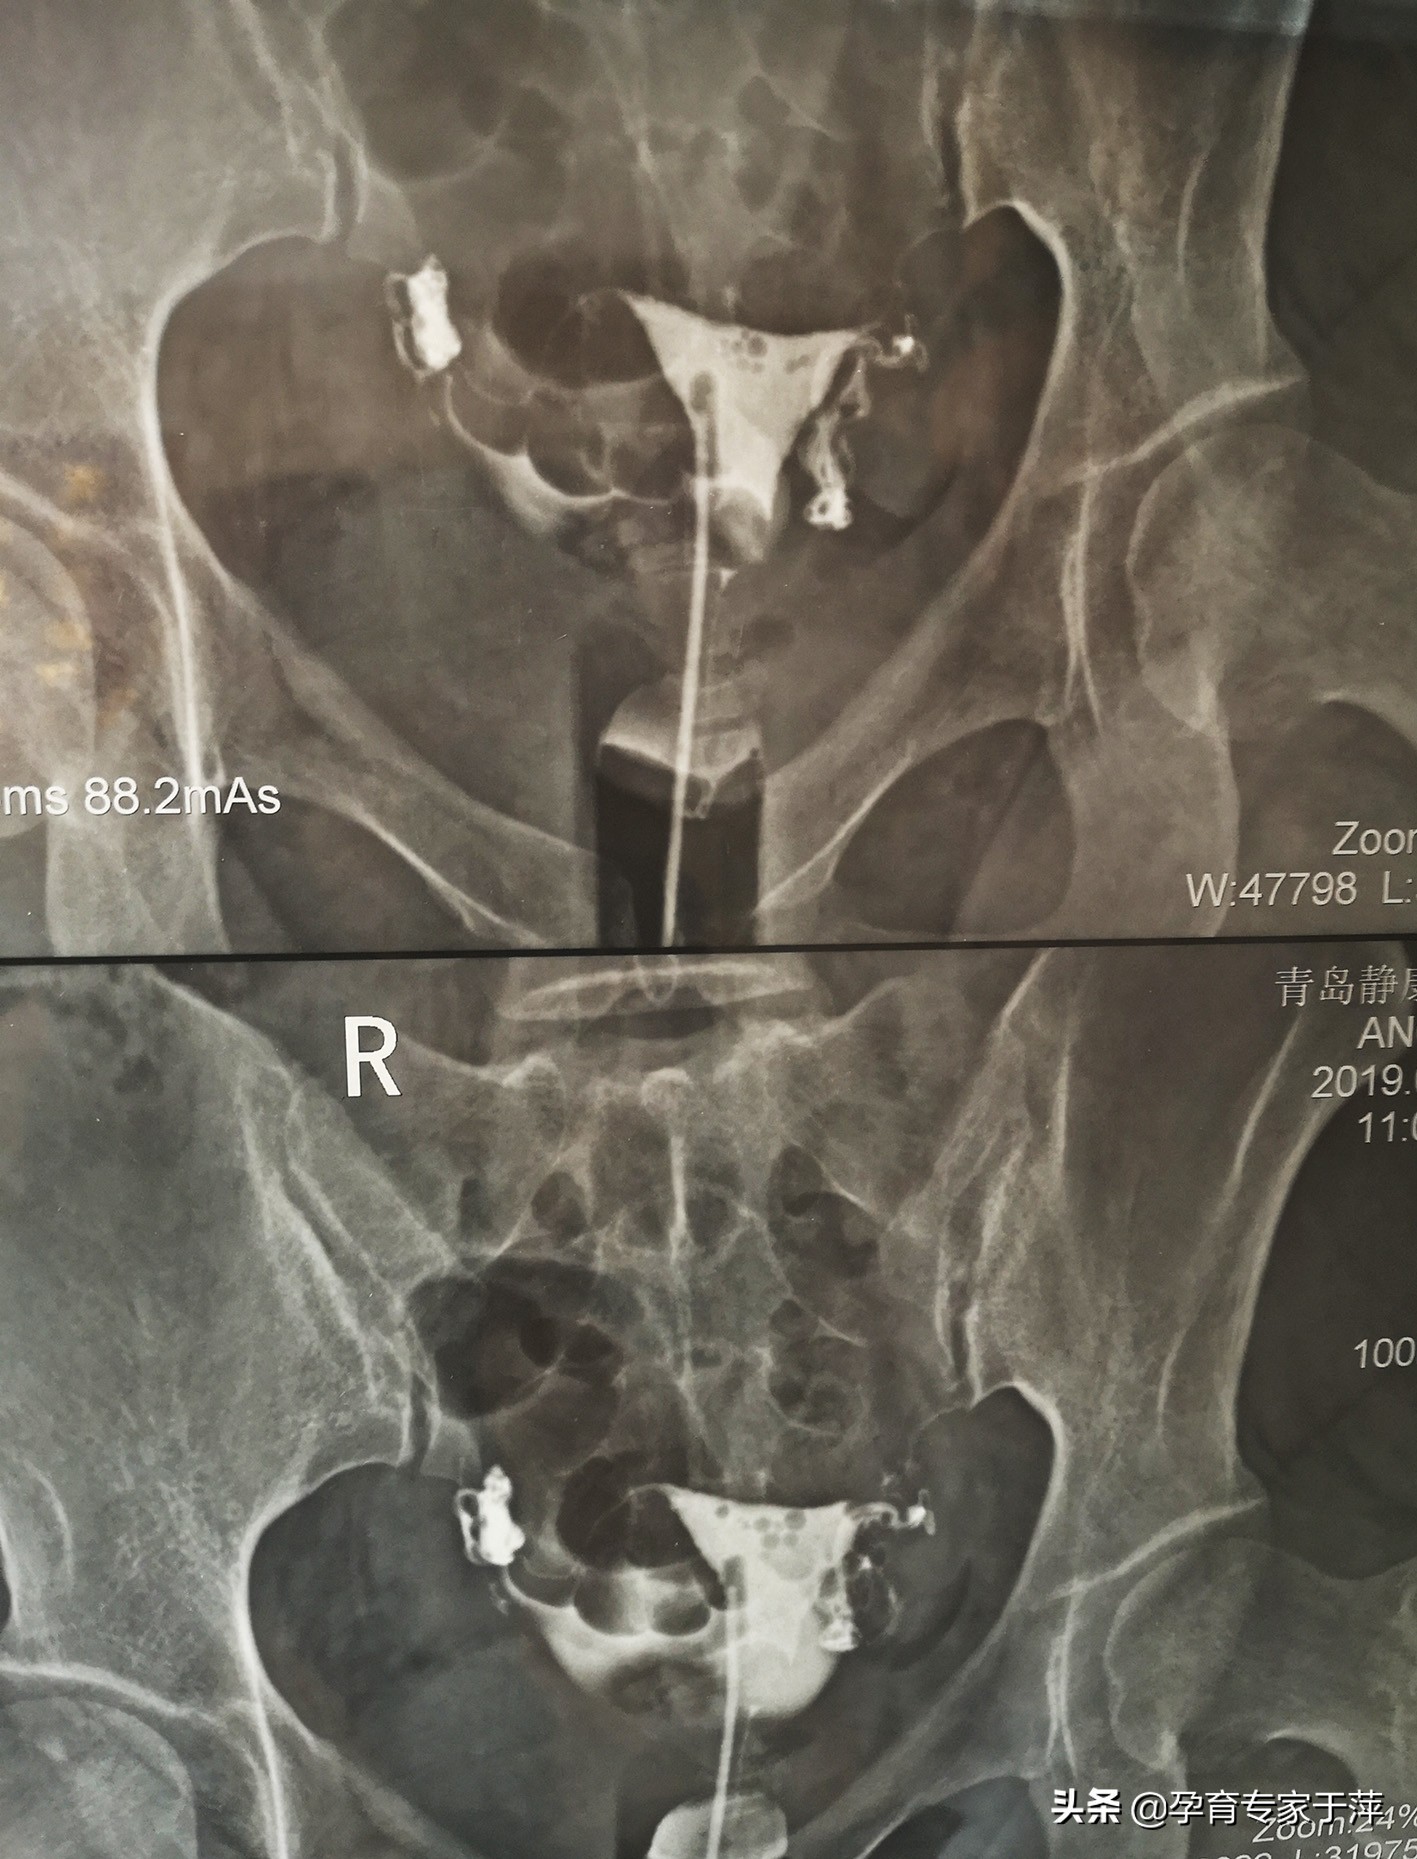

患者2019年3月来诊,夫妻双方共同做了检查,女方:影显示双侧输卵管通而不畅,右侧伞部粘连成团。查内分泌:促卵泡激素FSH 6.87mIU/ml,促黄体生成素LH 5.21 mIU/ml,泌乳素PRL43.77ng/ml,人抗苗勒试管激素AMH8.64ng/ml。并且卵巢B超显示卵巢多囊样变,结合患者长期月经不调的情况,确诊为:多囊卵巢综合征、双侧输卵管通而不畅、右侧伞部粘连成团。

通过中医口服、灌肠、外敷治疗输卵管的同时,西药调理患者内分泌,主要是要把泌乳素降下来。男方没有用药,回家调整饮食、生活习惯,配合运动改善液化不良的情况。治疗3个月复查,内分泌恢复正常,输卵管造影输卵管右侧通畅,左侧上举。之后开始试孕,在试孕的第一个月就成功怀孕了。因为患者之前曾胎停流产经历,这次怀孕后也比较担心,积极进行保胎治疗,现在B超胎心胎芽都挺好的,心里的大石头终于落下了。